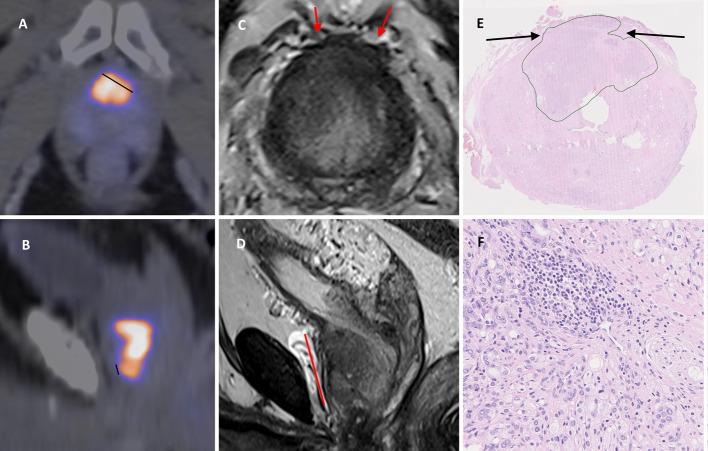

Positron emission tomography/computed tomography (PET/CT) with prostate specific membrane antigen ligands (PSMA) is established for use in primary staging of prostate cancer to screen for metastases. It has also shown promise in local tumor staging, including detection of extraprostatic extension (EPE) and seminal vesicle invasion (SVI). Previous studies have shown high heterogeneity in methods and results. Our aim was to compare [F]PSMA-1007 PET/CT to magnetic resonance imaging (MRI) in evaluation of EPE and SVI, building on a previously described method for standardized evaluation. We retrospectively included 124 patients who had undergone MRI, PSMA PET/CT and prostatectomy. PSMA PET/CT images were evaluated by two nuclear medicine physicians. Using a standardized method, they measured length of capsular contact (LCC) and assessed EPE and SVI visually with the use of 5-point Likert scales. A radiologist evaluated MRI images using criteria based on Prostate Imaging-Reporting and Data System version and incorporating LCC measurement and Likert scales. We evaluated diagnostic performance with histopathology as reference, and the interrater reliability of the PET evaluations.

The sensitivity and specificity for detecting EPE with the quantitative LCC method for PSMA PET/CT was 0.46/0.91, for the visual method 0.28/0.82 and for the combination of the two 0.54/0.76. AUC in ROC analysis for the LCC method was 0.70. For MRI the sensitivity and specificity were 0.80/0.64. For SVI, PET/CT and MRI had sensitivity and specificity of 0.14/1.0 and 0.50/0.92 respectively. The intraclass correlation coefficient for the PET LCC measurement was 0.68, the kappa values for the visual Likert scales for PET were 0.53 for EPE and 0.63 for SVI.

正电子发射断层扫描/计算机断层扫描(PET/CT)联合前列腺特异性膜抗原配体(PSMA)已被用于前列腺癌的初始分期以筛查转移灶。它在局部肿瘤分期方面也显示出前景,包括检测前列腺外侵犯(EPE)和精囊侵犯(SVI)。既往研究表明方法和结果存在高度异质性。我们的目的是在先前描述的标准化评估方法基础上,比较[F]PSMA - 1007 PET/CT与磁共振成像(MRI)在评估EPE和SVI方面的差异。我们回顾性纳入了124例接受过MRI、PSMA PET/CT和前列腺切除术的患者。PSMA PET/CT图像由两名核医学医师评估。他们使用标准化方法测量包膜接触长度(LCC),并使用5级李克特量表直观评估EPE和SVI。一名放射科医生根据前列腺影像报告和数据系统版本的标准评估MRI图像,并纳入LCC测量和李克特量表。我们以组织病理学为参考评估诊断性能,以及PET评估的评分者间信度。

PSMA PET/CT定量LCC法检测EPE的敏感性和特异性分别为0.46/0.91;视觉法为0.28/0.82;两者结合为0.54/0.76。LCC法在ROC分析中的AUC为0.70。MRI检测EPE的敏感性和特异性分别为0.80/0.64。对于SVI,PET/CT和MRI的敏感性和特异性分别为0.14/1.0和0.50/0.92。PET LCC测量的组内相关系数为0.68,PET视觉李克特量表评估EPE的kappa值为0.53,评估SVI的kappa值为0.63。